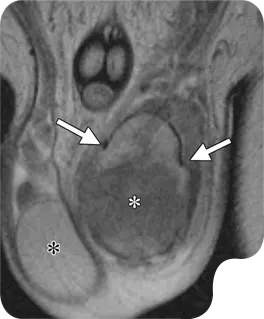

SCROTAL/TESTICULAR

This ultrasound examination focuses on the scrotum, the sac that contains the testicles, epididymis, and the spermatic cord. It is used to evaluate for abuses of course pain, swelling, or masses, such as testicular torsion, epididymitis, o hydroceles. Doppler imaging can be added to assess blood flow within the testicles, which is crucial in cases of suspected torsion.